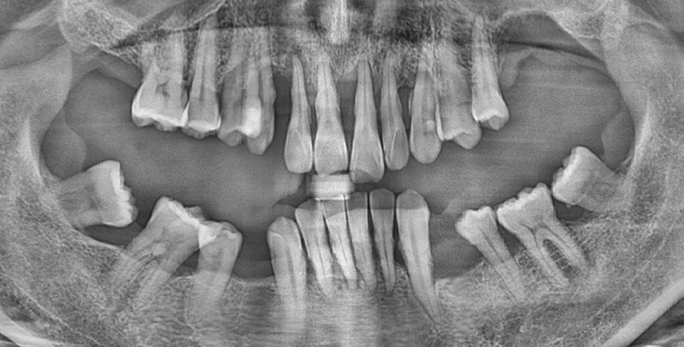

• 50대 초반 고혈압, 당뇨 남성 / 전치부 케이스